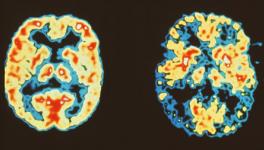

The researchers began with the hypothesis that brain atrophy starts at some vulnerable region and then spreads out to anatomically connected regions via the synapses. They scanned brains of the patients to find out where the brain atrophy had begun. To do this, they built standardised maps of some 175 brain regions using FMRI (Functional Magnetic Resonance Imaging) of 75 healthy persons. They then matched these standardised maps with the scans from FTD affected people and found out the hub of the brain atrophy as the likely epicentre of the patient’s degeneration.

They used the results from this step to predict in which direction the atrophy spreads and matched their predictions with the brain scans from the FTD affected people taken a year back. They found good matches in their predictions that were based on their hypothesis. The brain atrophy spreads through the brain by synaptic connections between related brain areas. The progression starts from a vulnerable region and eventually affects other parts.